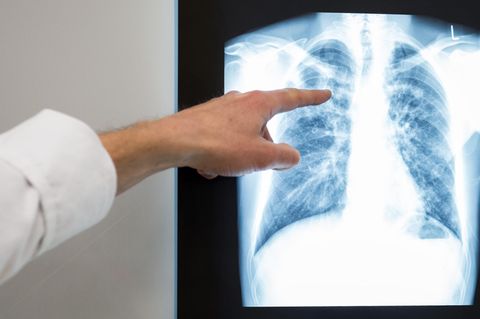

Tuberkulose auf einem Scan der Lunge.

© Getty Images/iStockphoto